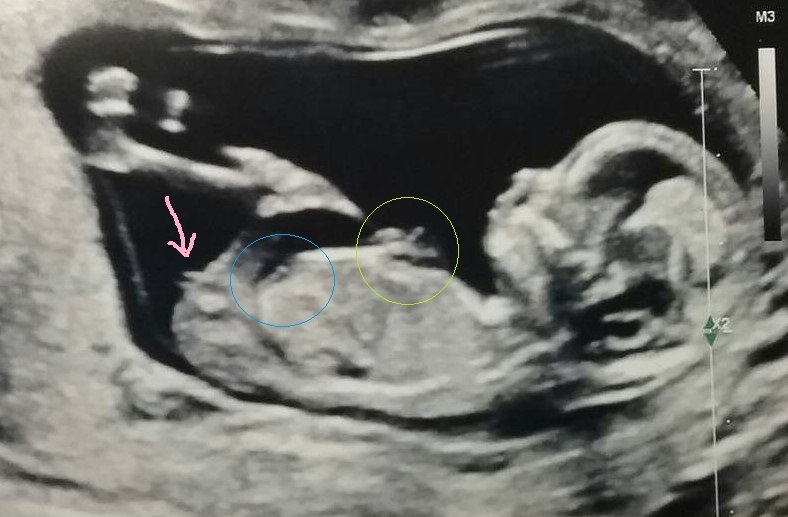

Maybe a girly nub, see picture:

I agree with Claire, it looks more girly. Although it isn't a clear shot of the nub so it is just a guess.